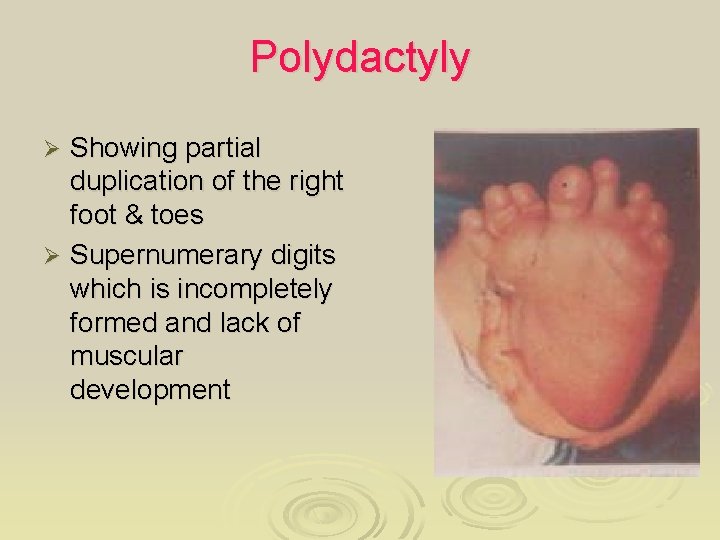

Polydactyly Showing partial duplication of the right foot & toes Ø Supernumerary digits which is incompletely formed and lack of muscular development Ø

Polydactyly Type: External Ø Region/Structure: Paw / Digit Ø Definition: Supernumerary digit(s) Ø